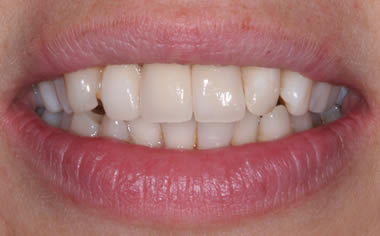

More front teeth replaced by dental implants

Case Three (4 images)